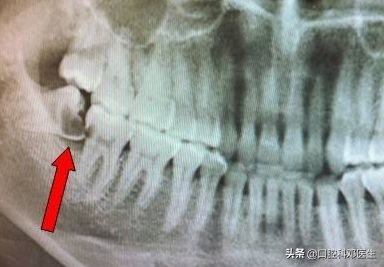

智齿没有足够的空间萌出,只能部分萌出,或者完全埋伏在骨头内,这就为智齿发炎留下了病根,只要抵抗力下降,就会引起细菌大量繁殖,引起智齿区域的疼痛。

很多人认为智齿是好好的牙齿,为什么要拔掉呢?或者是担心拔牙痛,一直下不了决心,导致越拖越厉害,引起了很多本不该出现的问题,比如留着智齿引起旁边牙齿的蛀牙、疼痛;留着智齿引起的囊肿、肿瘤;留着智齿引起的牙齿拥挤;留着智齿等到怀孕发炎时的痛不欲生;留着智齿引起的骨髓炎、面部瘘管等;